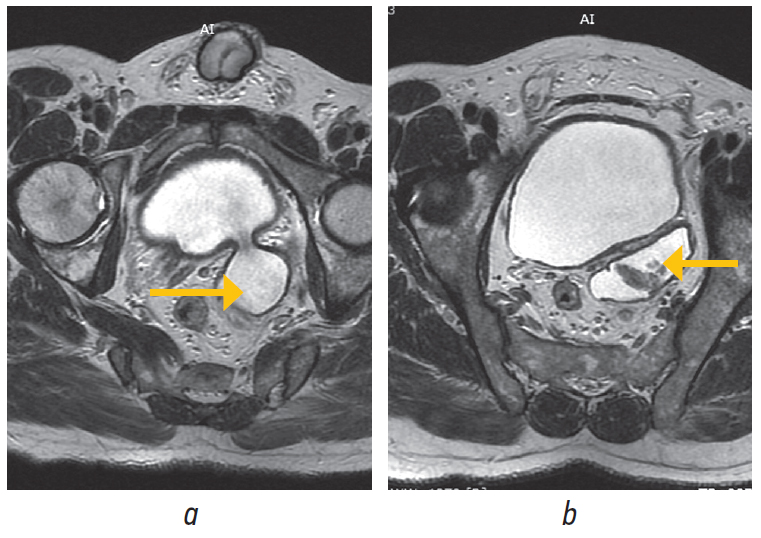

При магнитно-резонансной томографии определялся ДМП по задней стенке латеральнее устья левого мочеточника, с солидным образованием по типу «цветной капусты» по заднелатеральной стенке дивертикула, размерами 2,7 × 1,7 × 2,5 см, VI-RADS4, объем предстательной железы 31 см3 (рис. 8).

Рис. 8. Пациент Н., 49 лет. Магнитно-резонансная томография: a — дивертикул мочевого пузыря (указан стрелкой); b — новообразование дивертикула мочевого пузыря (указано стрелкой) / Fig. 8. Patient N., 49 years old. Magnetic resonance imaging: a — bladder diverticulum (indicated by an arrow); b — neoplasm of the bladder diverticulum (indicated by the arrow)